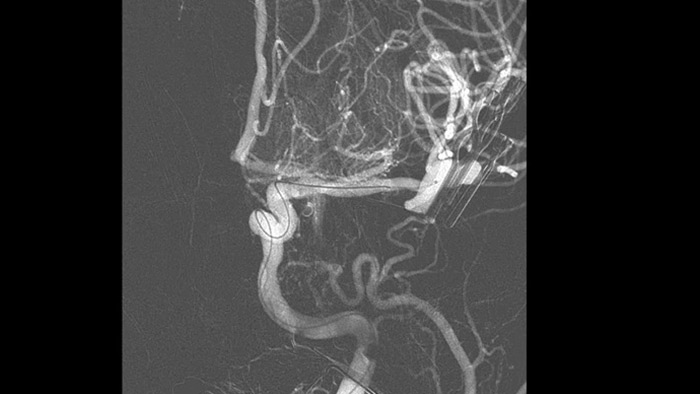

Imágenes nítidas con angiografía de sustracción digital (DSA) 2D con tecnología ClarityIQ

DSA 2D con tecnología ClarityIQ

ClarityIQ aplica la compensación automática del movimiento durante la angiografía de sustracción digital (DSA) en tiempo real para mantener imágenes nítidas de los vasos. Esto respalda la toma de decisiones fundamentadas durante los procedimientos de accidente cerebrovascular.

Visualización DSA

Las visualizaciones de DSA de alta calidad le permiten evaluar si ha recuperado el coágulo completo y si se han dispersado trozos de coágulo distalmente en el cerebro. Puede verificar la restauración del flujo sanguíneo a la penumbra y verificar si hay hemorragias periprocedimiento.